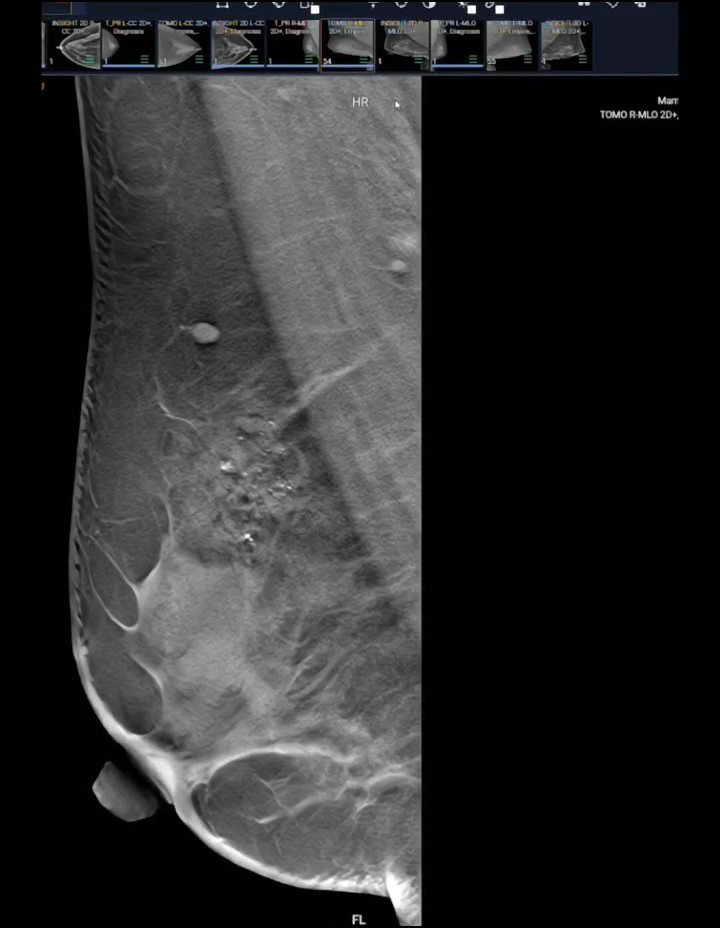

Sau khi siêu âm tuyến vú, bác sĩ chỉ vào màn hình và bảo tôi: "Đây là u xơ tuyến vú nhỏ, rất may em đi khám kịp lúc. Chỉ cần theo dõi định kỳ, chưa cần làm gì".